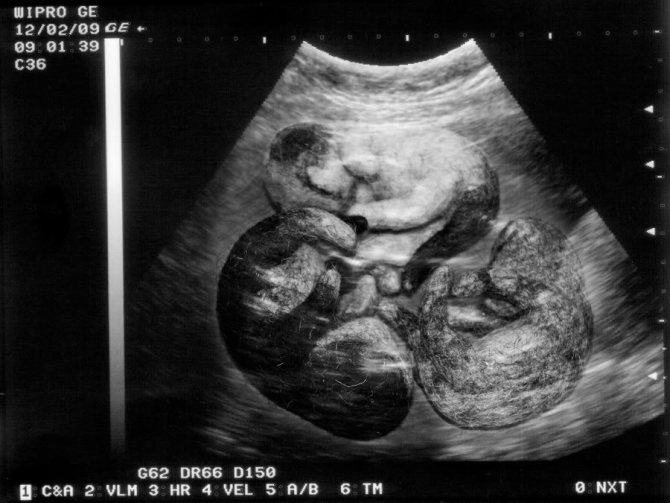

Котята в утробе на снимке УЗИ (18 недель)

К восьмой неделе соски сильно набухают, приобретают выпуклость. На животе может постепенно исчезнуть шерсть (покров возобновится после родов). Кошка уделяет много времени гигиеническим процедурам. Аппетит несколько снижается, поскольку плоды давят на внутренние органы.

Эмбрионы котят